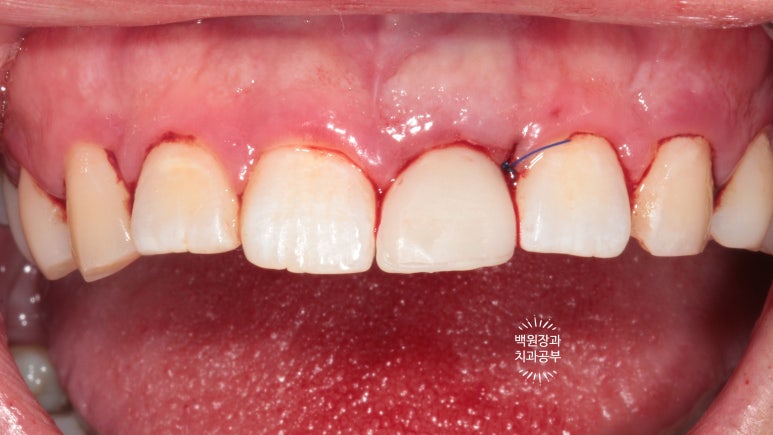

열흘 지나 실밥을 제거했을 때 보니 함께 시행했던 잇몸치료를 통해,

coral pink color를 회복한 건강한 잇몸과 보다 더 조화로워진 앞니를 볼 수 있었습니다.

생각보다 자연스러운 색의 치아와 (white esthetic) 잇몸의 색깔을 보실 수 있습니다. (pink esthetic)

옆에서 보면 왠지 치아 주변이 조금 검은듯한 느낌이 들기는 하나,

바로 옆에 위치한 또다른 가운제 앞니와 비교했을 때 큰 차이 없이 적절한 외형의 임플란트 보철물을 보실 수 있어요.